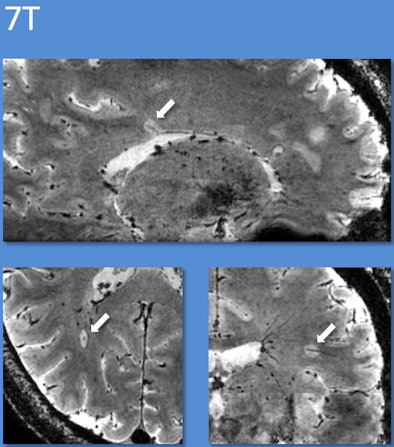

Specifically, deoxygenated blood in veins has different magnetic properties than oxygenated blood in arteries. Using a 7-tesla MRI technique known as T2*-weighted imaging, researchers can make veins appear especially dark, while MS lesions look bright. "Previously, it has not been possible to see this in live patients using a single brain scan," Mistry added. "Now, with T2* MRI, we can."

Using the 7-tesla MRI technique, 20 (80%) of the 25 patients could be diagnosed. Thirteen patients were diagnosed with MS; all of these patients had central veins visible in more than 40% of brain lesions. The seven patients with an eventual non-MS diagnosis had central veins visible in less than 40% of brain lesions.

| Using 7-tesla and 3-tesla T2*-weighted MRI, multiple sclerosis lesions characteristically had appearances reminiscent of a donut or coffee bean. Using guidelines based on counting a few of these characteristic lesions, the diagnosis could be correctly identified. Images courtesy of Dr. Niraj Mistry. |